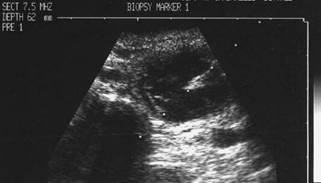

CITOaspiratIA ecogHIDATA

Noduli chistici

Barbat de 26 ani. Lobul drept al tiroidei: nodul chistic, anecogen cu intarire posterioara. Punctia se face in diagonala, acul traverseaza chistul spre de la suprafata spre baza si de la dreapta spre stg.

Imaginea dupa insertia acului. Varful acului este in centrul leziunii. Examen citologic: leziune benigna.